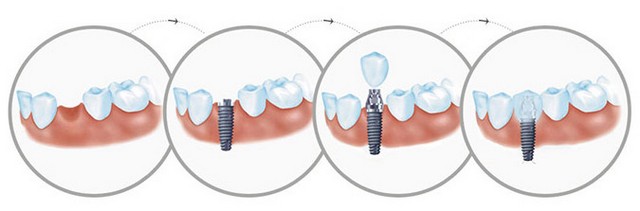

微创种植牙作为目前较 受欢迎的牙齿缺陷修复手术之一,因其“即拔即种,即种即食”标准得到很多人的宠爱,但是不少人也怀疑:微创种植牙真的有说得这么好吗?

康贝佳医生介绍到:微创种植牙是目前常用的一种牙齿缺陷修复手术,而且在我们的生活当中微创种植牙也是施行较多的一种手术,被认为使目前理想的美容修复方法。

1、不磨牙:依靠自身的人工牙根进行修复,不用磨旁边的健康牙齿,对牙齿没有任何伤害。

2、舒适方便:不使用活动假牙必需的基托与卡环,没有异物感,非常舒适、方便,而且有利于保持口腔的清洁卫生。

3、稳固耐用:不使用传统镶牙的卡环或牙套,人工牙根牙槽骨紧密结合,像真牙一样扎根在口腔里,具有很强的固位力与稳定性,而且能很好地恢复牙齿功能,咀嚼功能大大优于其他传统假牙。

4、时间短:采用局部麻醉,创伤小,术后即可进食,几乎苦。一般种植体植入术只需要几十分钟至数小时即可以完成。

5、无副作用:由于选用的是与人体相容性极好的生物材料,种植牙对人体不产生任何不良的副作用。

6、美观:可以根据就诊者的脸型、其他牙齿的形状与颜色制作牙冠,达到整体协调和美观的较 佳效果。